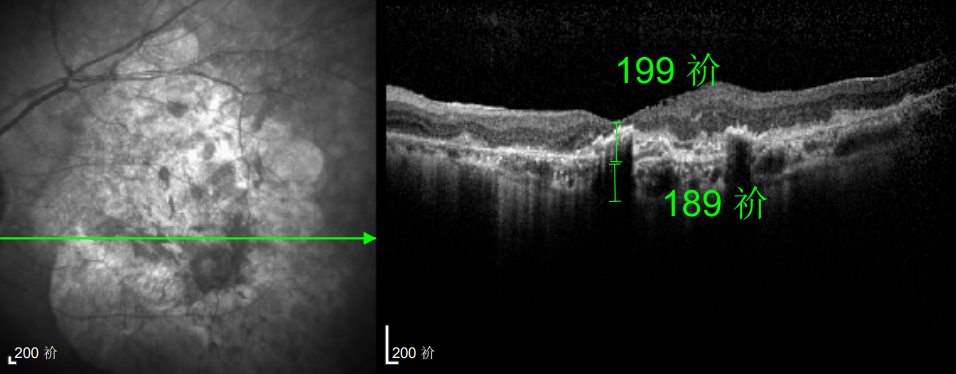

△延誤復(fù)查后的左眼